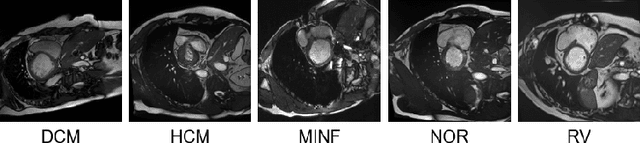

Rights provisioned within data protection regulations, permit patients to request that knowledge about their information be eliminated by data holders. With the advent of AI learned on data, one can imagine that such rights can extent to requests for forgetting knowledge of patient's data within AI models. However, forgetting patients' imaging data from AI models, is still an under-explored problem. In this paper, we study the influence of patient data on model performance and formulate two hypotheses for a patient's data: either they are common and similar to other patients or form edge cases, i.e. unique and rare cases. We show that it is not possible to easily forget patient data. We propose a targeted forgetting approach to perform patient-wise forgetting. Extensive experiments on the benchmark Automated Cardiac Diagnosis Challenge dataset showcase the improved performance of the proposed targeted forgetting approach as opposed to a state-of-the-art method.